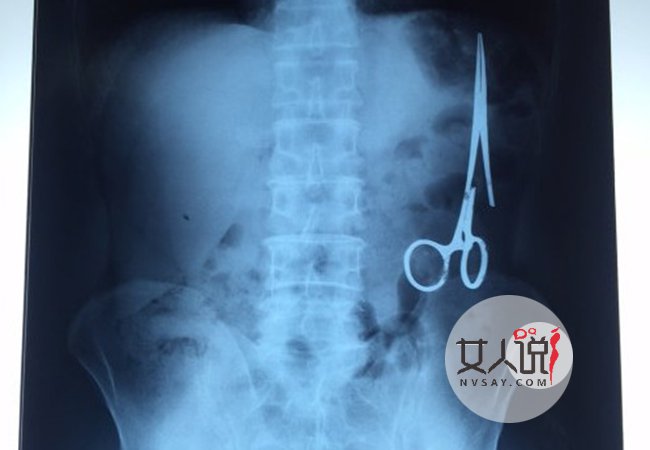

剪刀遗留腹中18年引起众人的注意,也纷纷讨论剪刀的来历。据了解男子腹中的剪刀已经存留18年了,但是从来都没有感到任何的剧痛,且剪刀在腹中已经和其他的器官连接起来了,如果不是出车祸去检查,或许这把剪刀遗留在腹中陪伴到死也没人知道,一起去看看男子腹中剪刀的来历。

据报道,在越南首都河内医疗专家的帮助下,越南东北部的太原省(Thai Nguyen)铸钢医院的医生日前从54岁患者M.V.N腹中取出一把医用剪刀。这把剪刀是此前曾为M.V.N手术的医生遗留的,已经在其腹中待了18年时间。